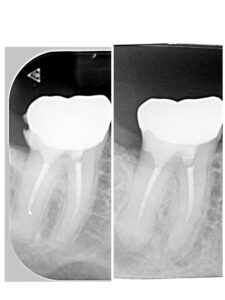

| 主訴 | 歯並びを治したい |

| 診断名 | 叢生(混雑した歯並び) |

| 年齢・性別 | 82歳、女性 |

| 治療期間・回数 | 4ヶ月間、来院回数4回 |

| 治療方法 | 歯と歯の間に0.5mmのやすりがけをして歯の横幅を修正し、マルチブラケット装置(ワイヤー矯正器具)にて歯を配列 |